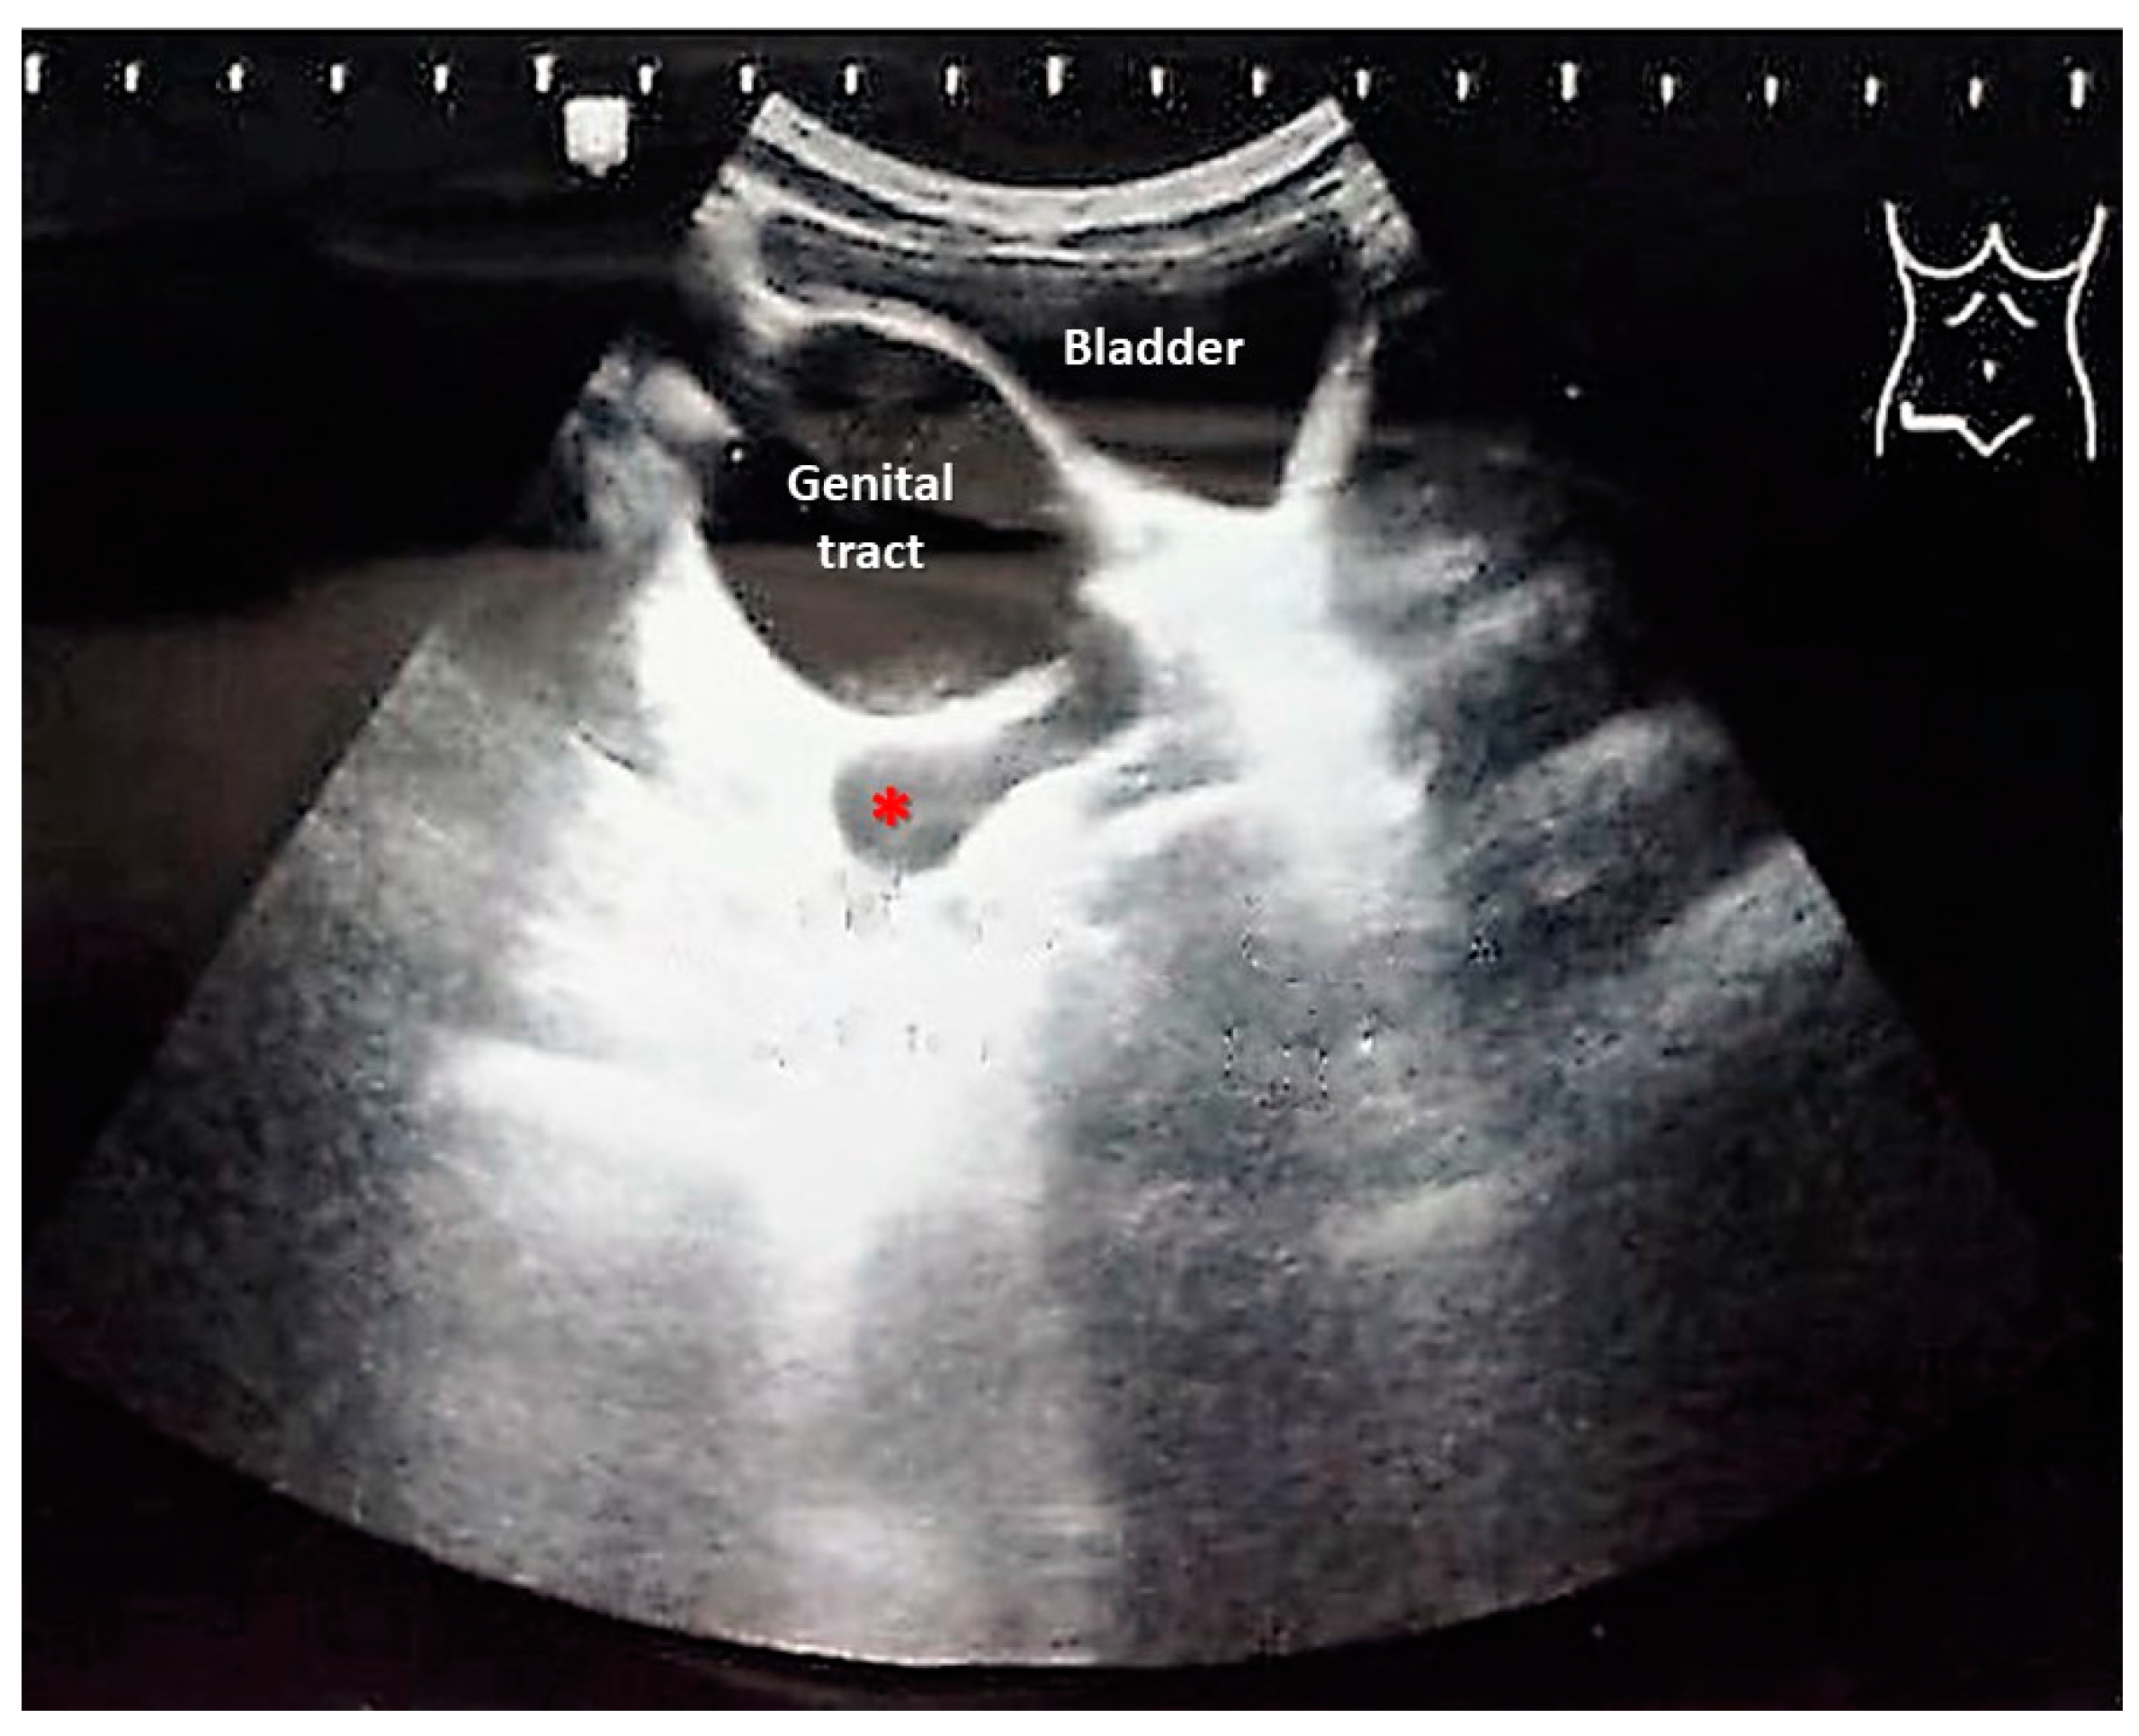

2. Case Presentation